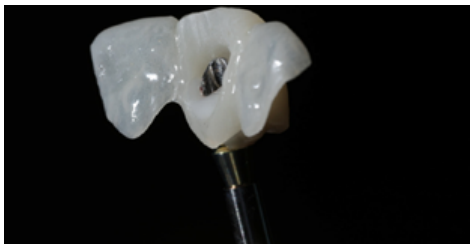

Different protocols have also been established for the management of the anterosuperior aesthetic sector, in addition to performing the immediate implant and provisional crown, including placing material between the OII and the buccal cortical to minimise possible collapse and the management of peri-implant soft tissue8-11.